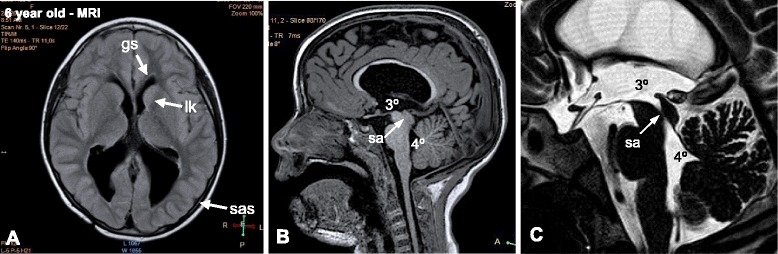

A MRI performed at 6 years of age showed obliteration of the SA, mild dilatation of the lateral ventricles, a normal subarachnoid space, signs of periventricular leukomalacia in the frontal horns of the lateral ventricles, and a zone suggesting a glial scar in the frontal subcortical zone (Fig. 2).

Fig. 2.

MRI findings at 6th years of age. a MRI (transverse T1 imaging) showing mild ventricular dilatation, a normal subarachnoid space (sas), signs of periventricular leukomalacia (lk) in the frontal horns of the lateral ventricles, and a glial scar (gs) in the frontal subcortical zone. b, c MRI (sagittal T1 and sagittal T2 imaging, respectively) showing complete obliteration of the SA